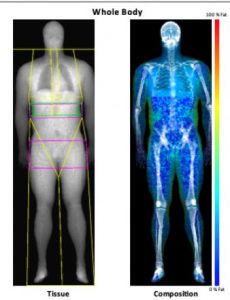

The gold standard of measuring body composition, DEXA (dual energy x-ray absorptiometry) scans are the most accurate way to measure bone density, muscle mass, fat around your organs and total body fat. DEXA scans are not altered by hydration status, bloating, how much you have eaten that day, or any other temporary change that can affect other methods of body composition measurement.

An example of a DEXA body composition scan from Body and Bone.